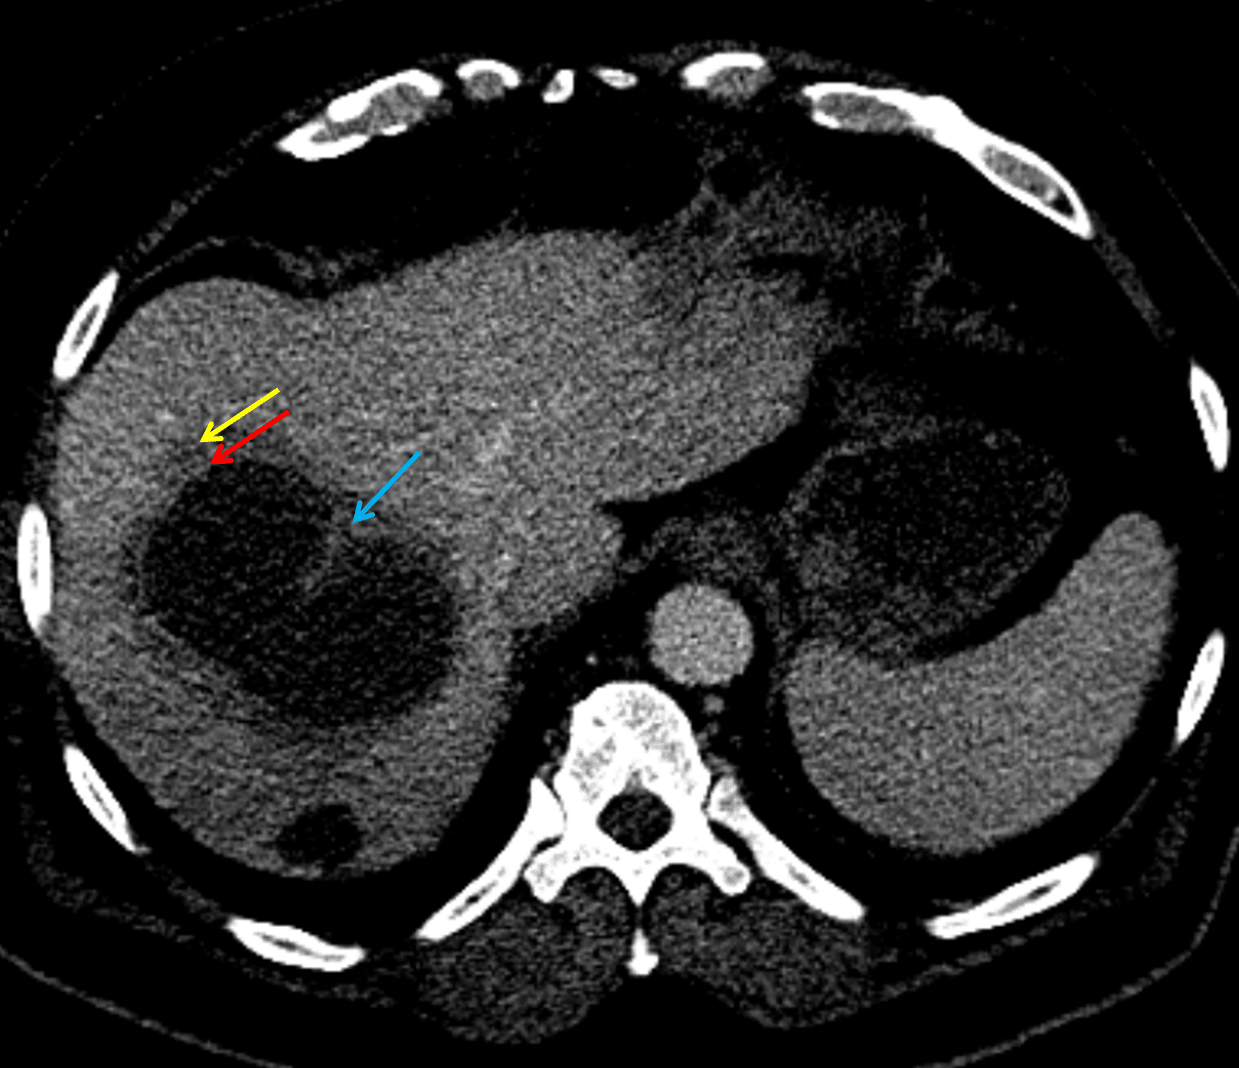

- The classic CT imaging appearance is a double target sign with internal low density surrounded by an internal enhancing rim (capsule) and a low density external rim (edema)

Hepatic abscess showing the double target sign with low density internally surrounded by a thin inner enhancing rim (red arrow) and ill-defined outer low density rim (yellow arrow). Blue arrow indicates an internal septation.